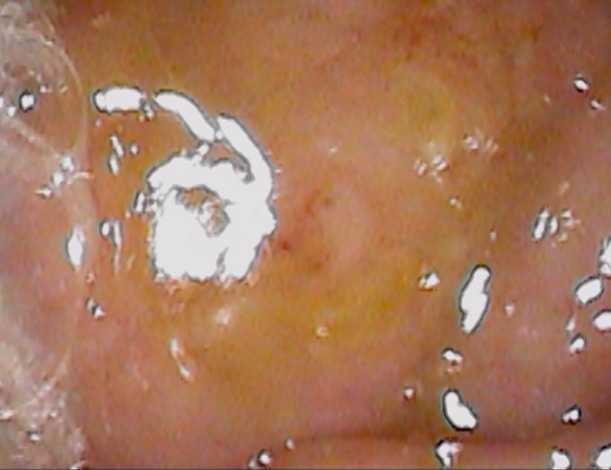

これです↓

この黄色の丸印です。

鉗子付きファイバーで摘出しました。